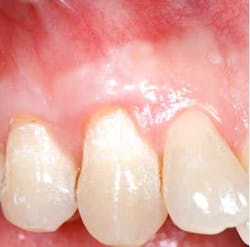

According to the proceedings from the 2014 American Academy of Periodontology Regeneration Workshop, root coverage may be attained through the application of a variety of surgical procedures. These outcomes are generally measured by reduced defect depth, gain in clinical attachment, and an increase in keratinized tissue. The associated systematic reviewprovides clear evidence that a subepithelial connective tissue graft (SCTG) procedure offers the best outcome for mean and complete root coverage, as well as an increase in keratinized tissue. (4,5) Strong evidence also supports biomaterials such as acelullar dermal matrix grafts (ADMG) or enamel matrix derivative (EMD) in conjunction with a coronally advanced flap (CAF) that can be used as an alternative to treat Miller Class I and II single-tooth gingival recession defects (figures 1 and 2). (6)Another suggestion from the proceedings was that using a split-thickness flap or tunnel technique can help to revascularize the graft by maintaining an excellent vascular supply to the flap.